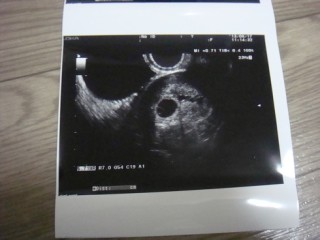

胎芽の大きさ2.1mm

心拍も確認できました!